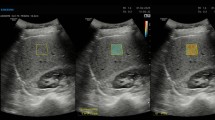

Following this finding, we paid close attention to small ROIs showing marked deviation from the normal case (the theoretical Rayleigh distribution). To analyze the distribution of these small ROIs within the liver, we used computer program specifically developed for this purpose (making use of the above-mentioned principle of ASQ). With this program, the small ROIs showing a degree of deviation higher than the cut-off level were represented in red overlaid on B-mode images (Fig. 3). In this study, the diameter of each small ROI was set at about 1 mm, approximately equal to the liver nodule level, and the cut-off level was set at 200%. The red scatter thus obtained on B-mode images was called “US-Red”.

To objectively compare the share of US-Red, the percentage of the analyzed region of a B-mode image occupied by the US-Red was calculated (US-Red%). The analyzed region of a B-mode image was set in the vicinity of the focused area with dimensions of 1.75 × 1.75 cm.

Biopsy specimens from two cirrhotic patients with different US-Red% were examined in detail (Fig. 8). In Case 1, US-Red was markedly seen on the color image (Fig. 8a), with US-Red% being as high as 9.8%. The liver biopsy specimen (Fig. 8b) of this case was rated as “large” in terms of nodule size and “thick” in terms of fibrous septum thickness. In Case 2, on the other hand, US-Red was less marked on the color image (Fig. 8c), with US-Red% being low (4.0%). The liver biopsy specimen (Fig. 8d) of this case was rated as “small” in terms of nodule size and “thin” in terms of fibrous septum thickness. Thus, pathological differences were noted between Cases 1 and 2.